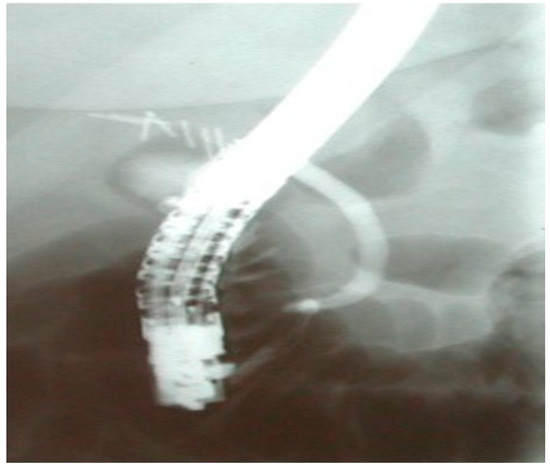

Bile Leak: Is There Optimal Timing for Endoscopy?

Background and Objectives: Bile leak is a common complication after hepatopancreatobiliary surgery, requiring timely management to prevent life-threatening outcomes. Endoscopic retrograde cholangiopancreatography (ERCP) is essential in treatment, but large data concerning optimal timing and technique selection are unavailable. This study evaluates whether [...] Read more.

Background and Objectives: Bile leak is a common complication after hepatopancreatobiliary surgery, requiring timely management to prevent life-threatening outcomes. Endoscopic retrograde cholangiopancreatography (ERCP) is essential in treatment, but large data concerning optimal timing and technique selection are unavailable. This study evaluates whether the timing of ERCP influences healing and if different bile duct injuries affect outcomes. Materials and Methods: Data from a prospectively maintained database over 25 years (2001–2025) included 176 patients (M/F: 91/85, mean age 62) undergoing ERCP for bile leaks. Results: Most leaks followed cholecystectomy (n = 143, 81.5%). The median time from leak to ERCP was 7 days. Ten patients (5.7%) had complete common bile duct (CBD) transection—considered major leaks—requiring surgery. Among the 166 minor leaks, the cystic duct stump (40.1%) was the most common injury site, followed by the CBD (24.1%) and the gallbladder bed (15.4%). Healing occurred in 90.6%. Stent placement improved healing rates (93.9% vs. 75.9%, p = 0.007), with no difference between pig-tail and (Amsterdam) straight plastic stents (90% vs. 96%, p = 0.267). Retained CBD stones or CBD strictures did not affect outcomes. Leaks from the cystic duct stump had a 96.9% resolution rate, whereas gallbladder bed leaks healed in 88%. The median healing time was 2 days, unaffected by stent placement or ES alone (p = 0.842), but later ERCP correlated with longer healing (RR: 0.362, p < 0.001). Following a right aberrant bile leak, the time for healing was longer than in leaks from other sites. Conclusions: ERCP with stenting remains the first-line approach for minor bile leaks. Early ERCP accelerates healing, emphasizing the importance of prompt intervention. Full article

(This article belongs to the Special Issue Recent Advances in Digestive Endoscopy)

Figure 1